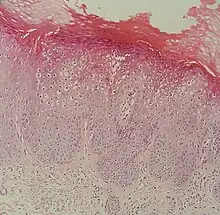

At histopathology, flat warts have cells with prominent perinuclear vacuolization around pyknotic, basophilic, centrally located nuclei that may be located in the granular layer.[4] These are referred to as "owl's eye cells."[4]